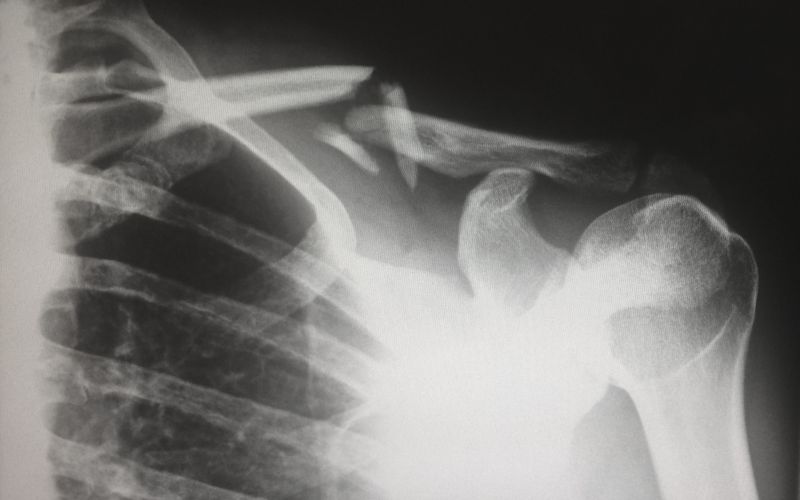

Материал, созданный учеными Курчатовского института предназначен для восстановления губчатых костей.